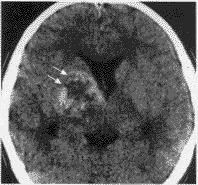

二、囊变、坏死与出血: 11例中5例肿瘤内可见囊变、坏死灶。CT图像上表现为水样低密度影(图1,2),MR上则为混杂性长T1和长T2信号影(图3,4)。9例经MR检查者,T1加权像4例见肿瘤内有斑块样出血灶,表现为不规则形斑块样高信号强度影(图3)。

图1 右侧基底节生殖细胞瘤。平扫见肿瘤呈类圆形混杂密度影。

肿瘤内可见囊变坏死区(双箭头)

图2 静脉注入对比剂后见病灶呈轻度“花环”样增强(箭头)